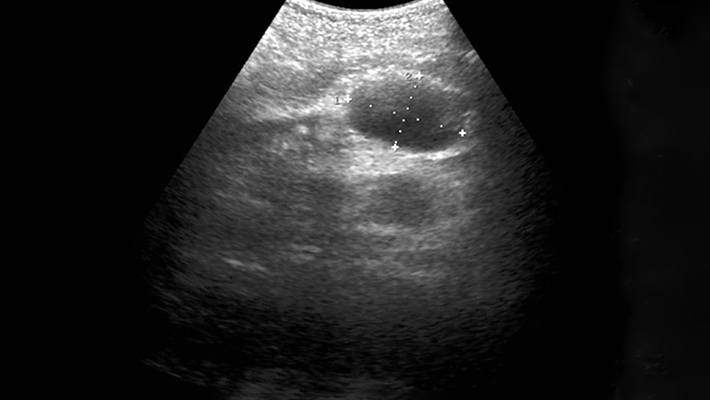

Ультразвуковое исследование (УЗИ) забрюшинного пространства — метод инструментальной диагностики, позволяющий оценить состояние органов и структур, расположенных позади брюшины. В частности, речь идет о почках, надпочечниках, мочеточниках, забрюшинных лимфоузлах, крупных кровеносных сосудах (аорта, нижняя полая вена), и поджелудочной железе. Метод широко используется в диагностике заболеваний мочевыделительной, пищеварительной, эндокринной и других систем организма.